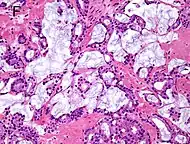

Intraductal carcinoma of the prostate with an infiltrative growth pattern may be morphologically difficult to distinguish from invasive cancer. One focus shows comedonecrosis (arrow), morphologically suggesting Gleason pattern 5 invasive carcinoma (a haematoxylin and eosin, b CK5/6)[19]